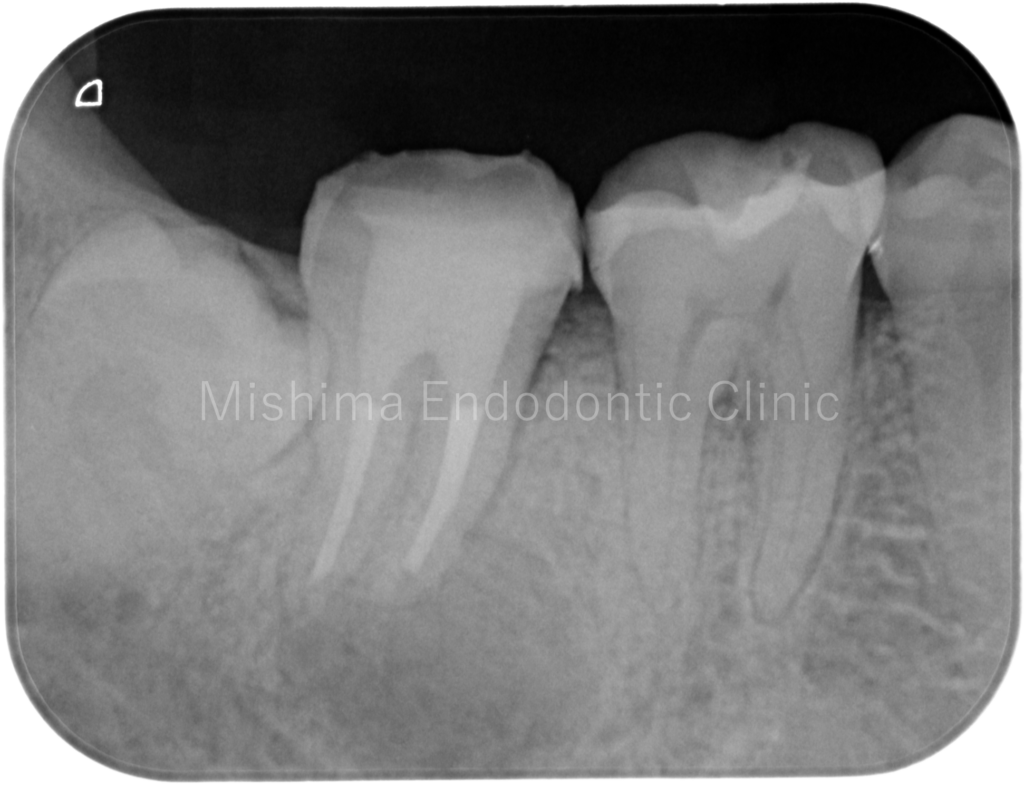

| 治療内容 | 既根管治療歯で比較的大きな根尖病変を認めた。根管治療は貼薬無しで即日根管充填。 術後、根尖透過像は消失し経過は良好。 |

術後1年